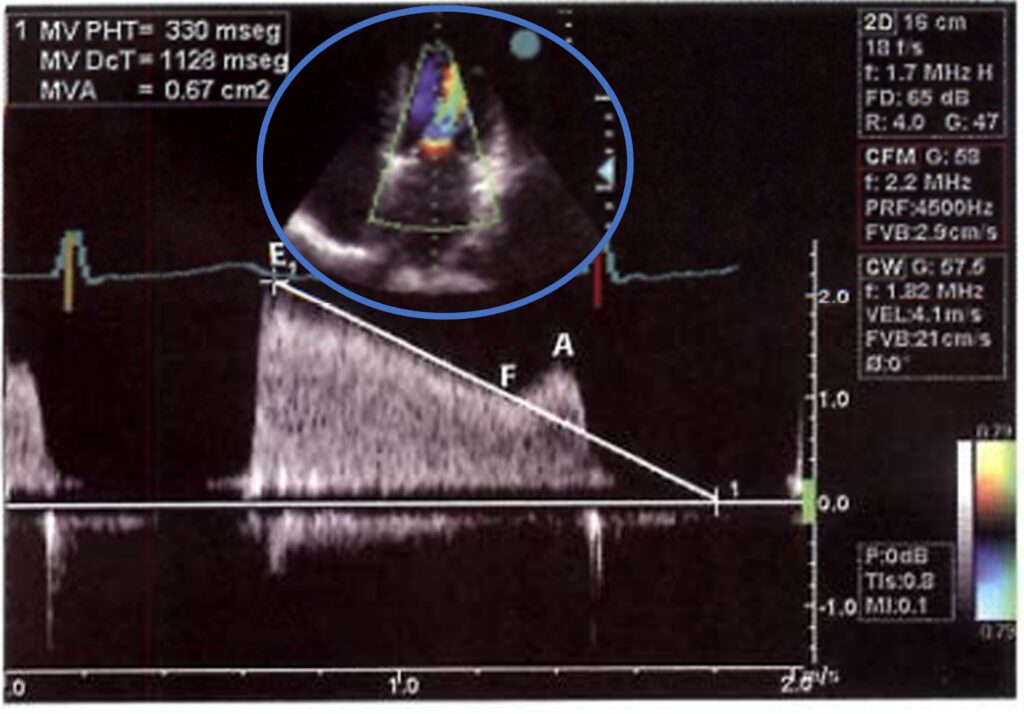

PRESSURE HALF-TIME (PHT):

Em pacientes com ritmo regular pode ser utilizado a medida do tempo em que o gradiente pressórico transmitral cai pela metade.

Na posição apical, com o color Doppler, escolhe-se a posição que permita o melhor alinhamento entre o fluxo diastólico mitral turbulento e o feixe de ultrassom.

Com o Doppler contínuo (ou pulsátil) registra-se o traçado espectral do fluxo transmitral. Quando utilizado o Doppler pulsátil, deve-se tomar o cuidado de posicionar o volume-amostra ao nível da vena contracta.

Posiciona-se o calibrador de aferição do equipamento no ponto de maior velocidade do fluxo e tangencia-se cuidadosamente a rampa de desaceleração do fluxo (segmentos E-F da curva de fluxo mitral).

Em alguns pacientes, principalmente os que apresentam dupla disfunção mitral, frequentemente a rampa de desaceleração protodiastólica é mais inclinada do que a porção mesodiastólica.

Nestes casos, a aferição do PHT deve ser realizada na porção mesodiastólica do traçado.

Esta medida é influenciada por fatores como retardo do relaxamento ventricular esquerdo, alterações do acoplamento atrioventricular (bloqueios atrioventriculares), duplo enchimento ventricular (insuficiência aórtica associada a estenose mitral), regurgitação mitral significativa e taquiarritmias.